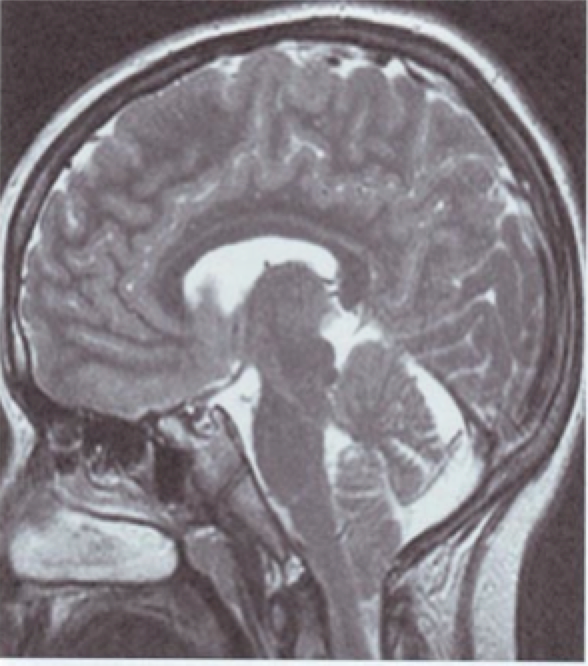

Perhatikan Gambar di bawah ini. Diagnosis manakah yang paling mungkin?

A. Sklerosis tuberus

B. Pakigiria

C. Invaginasi basilar

D. Malformasi Chiari I

E. Malformasi Chiari II

D